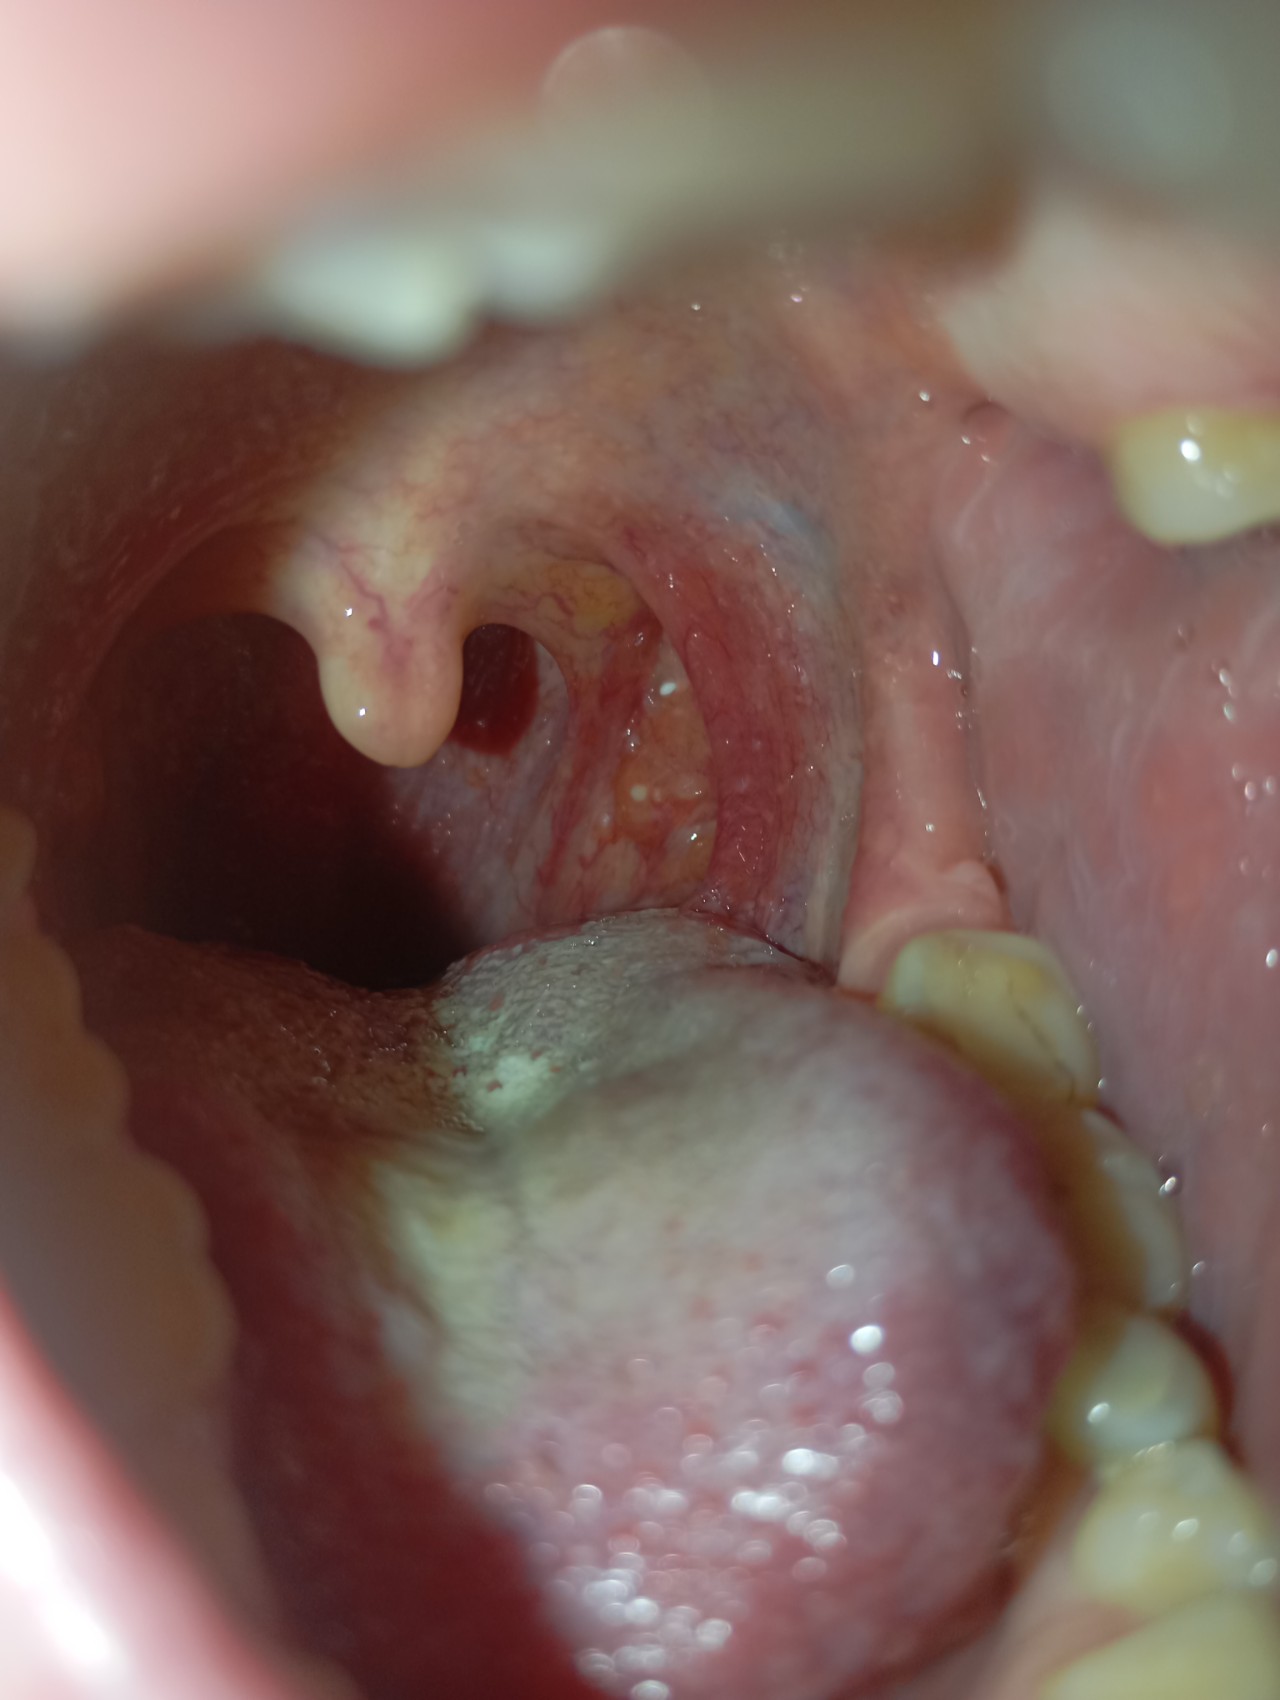

Здравствуйте, недавно стало першить в горле совсем немного, чуть покашливала. Посмотрела в зеркало и обнаружила около миндалины, чуть сбоку, какое -то образование, как маленький нарост, не отличающийся по цвету от остальной ткани. Подскпжира, пожалуйста, это нормально? Очень переживаю, спасибо!